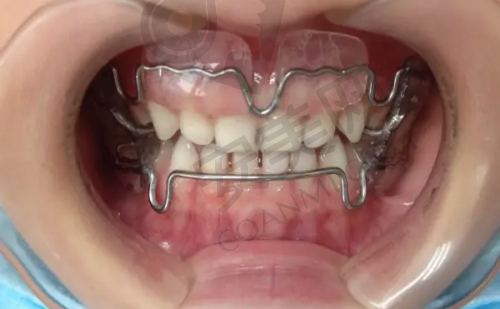

三亚舒诺口腔医院开展的诊疗项目涵盖了口腔的多个领域。种植牙方面,从单颗到全口种植都能提供服务,并且提供多种品牌的种植体,满足不同患者的需求。比如对于单颗牙齿缺失的患者,可以选择合适的种植体进行修复;而对于全口牙齿缺失的患者,医院也有专精的方案来解决问题。牙齿矫正包括隐形矫正、金属托槽矫正等,能满足不同年龄段患者的需求。隐形矫正美观舒适,适合对美观要求较高的患者;金属托槽矫正则价格相对较为亲民,矫正成效也十分显著。牙齿美白采用精良的美白技术,让您的笑容更加迷人。通过专精的美白方法,可以有效去除牙齿表面的色斑和污渍,使牙齿变得更加洁白亮丽。儿童齿科专为儿童设计了口腔保健服务,确保孩子们在愉悦的环境中接受治疗。医院会采用一些有趣的方式来吸引孩子的注意力,减轻他们对看牙的恐惧。牙周治疗针对牙周疾病提供专精的治疗方案,帮助患者解决牙龈出血、牙周炎等问题。